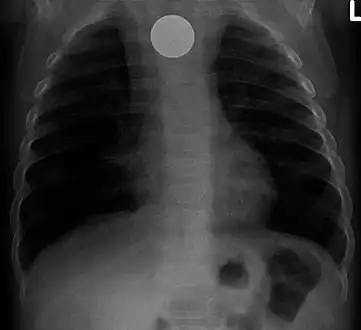

Chest radiograph showing a Venezuelan 25 cent coin lodged in the upper esophagus of a 9-year-old girl.

A coin seen on AP CXR in the esophagus